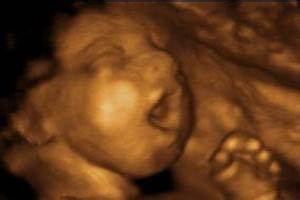

四維彩超檢查的目的?西寧生殖保健醫院專家指出:四維彩超是當代較為先進的檢查設備。可以檢查出胎兒的發育狀況,是準父母和大夫的好幫手,其越來越收到準父母的青睞。那么,四維彩超的檢查目的是什么呢?

4、可清楚地看到寶寶的外觀,尤其是表面的彎曲處,如臉部、鼻子、嘴唇、四肢、肚子等部位,觀察是否有畸形。

5、在四維彩超上可以清楚的看到寶寶的摸樣,寶寶的動作,所以說這份檢查報告也可以稱為寶寶的“零”歲相冊,甚至可以刻錄成光盤十分有紀念意義。